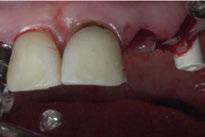

Para ilustrar el proceso, presentamos el caso de una mujer joven diagnosticada de carcinoma adenoide quístico en la región posterior del hemipaladar izquierdo (Figuras 1 y 2). El procedimiento quirúrgico realizado fue una

maxilectomía parcial que incluyó las piezas 24-26 y desde el reborde alveolar hasta la base del cráneo (Figuras 3 y 4). En este caso, la órbita y el globo ocular pudieron ser preservados. La reconstrucción inmediata se realizó mediante un colgajo de músculo temporal homolateral (Figura 5) y el defecto de la fosa temporal fue cubierto mediante una malla de titanio. Posteriormente, la paciente recibió radioterapia (Figuras 6 y 7). 2 años más tarde se diseñó un IS con anclaje en el arbotante nasomaxilar, zona subnasal izquierda

Figura 3. Maxilectomía parcial.

Figura 4. Defecto maxilar tras resección del tumor.